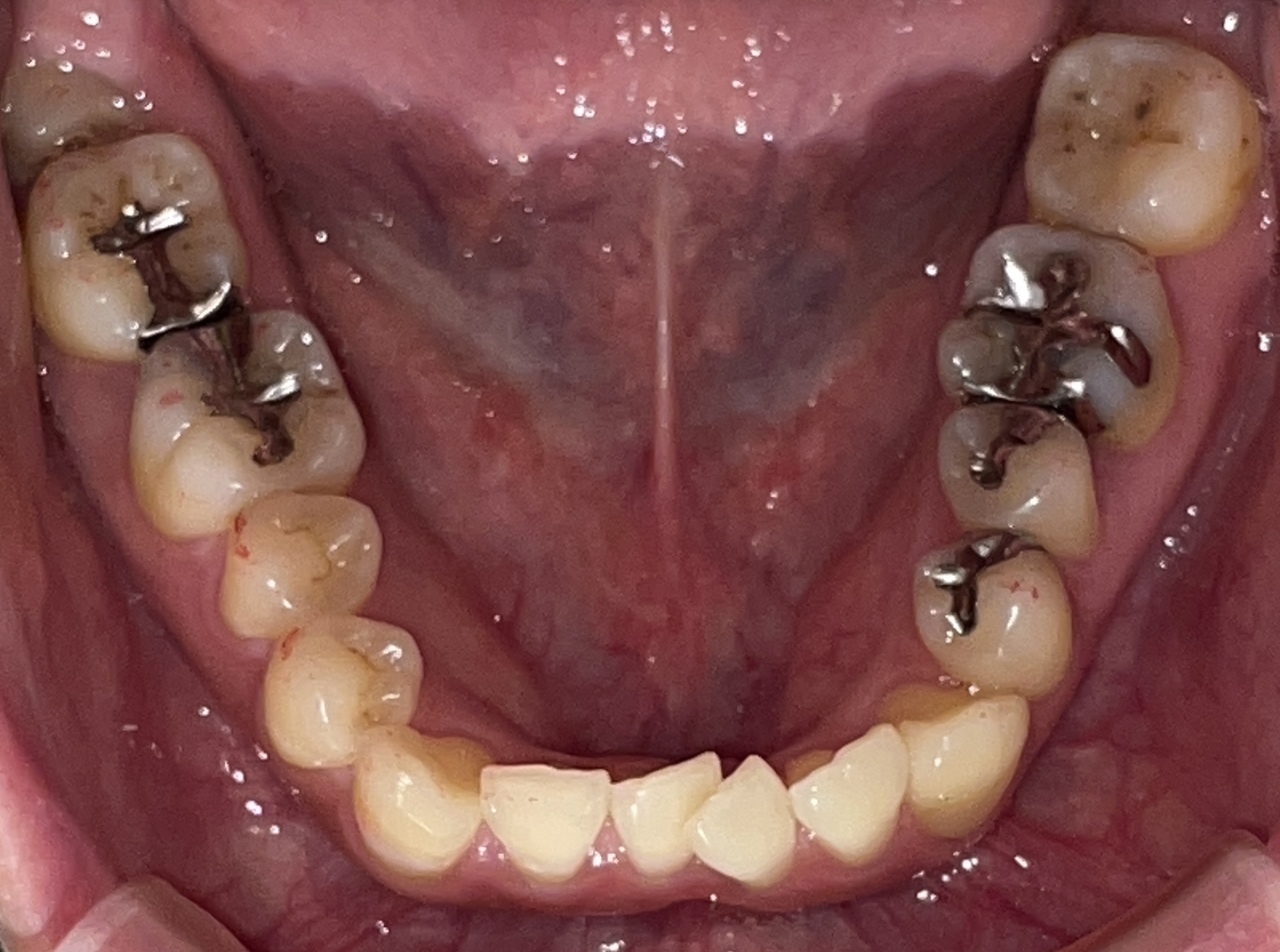

Before

After

矯正の種類 / invisalign GO

年齢・性別 / 30代女性

主訴  /  叢生、交叉咬合

治療期間 / 17ヶ月

費用 / 簡易検査 5,000円(税別) 精密検査 30,000円(税別)

両顎マウスピース 450,000円(税別) 両顎リテイナー料 60,000円(税別)

※マウスピース交換時別途調節料5,000円(税別)

副作用 / 口内炎・歯の移動に伴う痛み・知覚過敏 ※数日で収まる場合が多いです

リスク / 後戻り防止の為、夜のみマウスピースで保定を指示